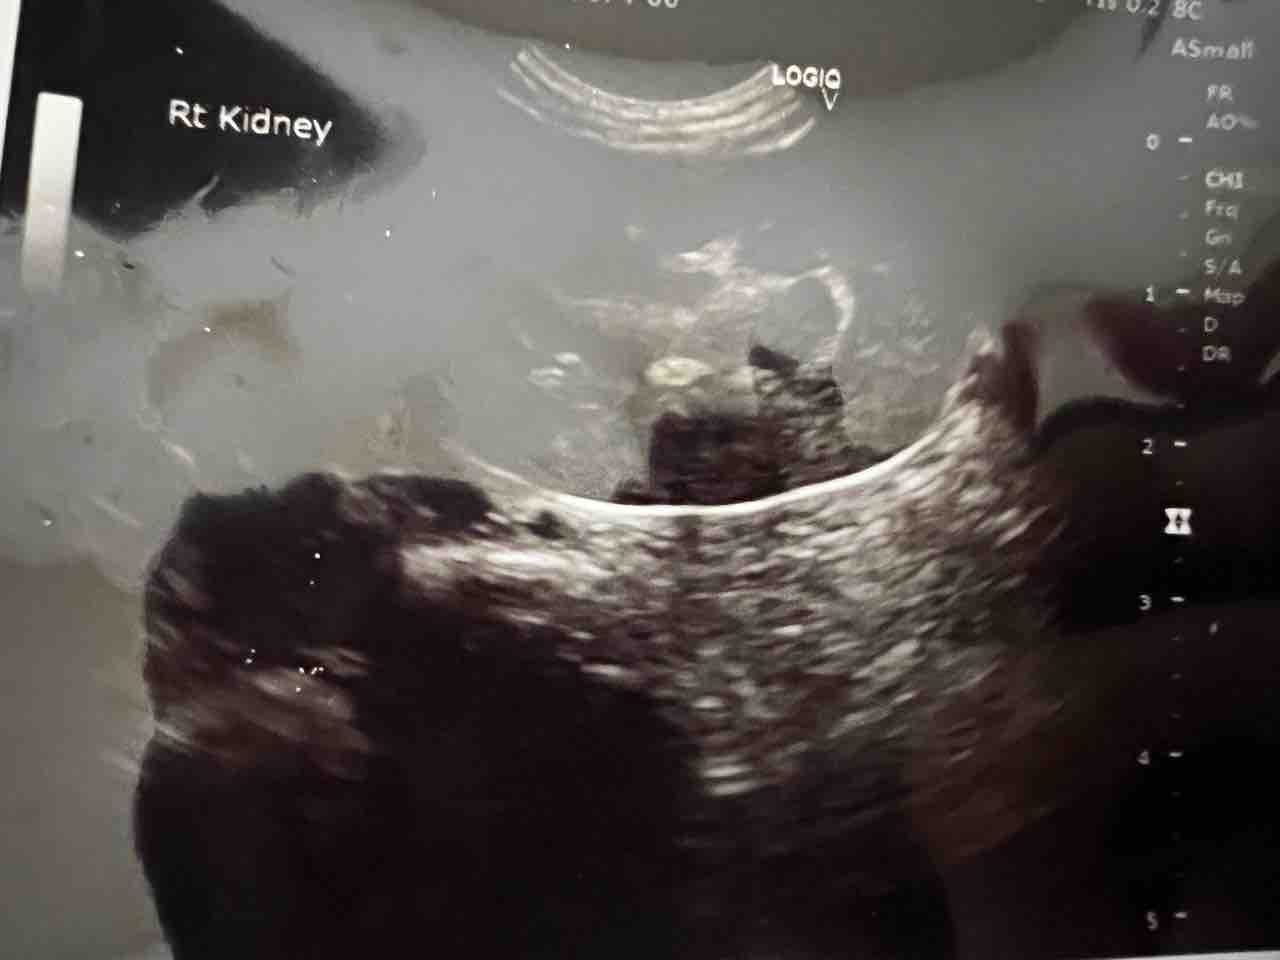

睾丸摘出術(除睾術・玉抜き) 当院の睾丸摘出術は治療目的・及び今後の治療を見越した術式で行いますので、 単に睾丸摘出のみを行う治療とは根本的な方法が違っております。 将来女性器まで形成したいが、とりあえず睾丸摘出で男性ホルモンを抑え精巣(睾丸)の痛みや違和感、しこり、腫れなどの症状の診断や治療の役に立ちます。精巣や 精巣上体 ※1 の形や大きさ、内部の評価、精巣周囲の血管を調べます。この検査により、精巣癌、精巣捻転、精巣上体炎、陰嚢水腫、精液瘤などがないかが分かります。睾丸が腫れていたり、触ると痛みを感じる場合は、睾丸や副睾丸(精巣 上体)の異常です。精巣捻転症(緊急を要す)、副睾丸炎(発熱を伴う)、 が疑われます。成人ではおたふく風邪のウイルスによる精巣炎(高熱)のこともあります。 精液に血が混じる、茶色の精液が出る(血精液症) �

Chapter4 精巣・陰嚢の病変|HitachiAloka Medical 超音波検査法セミナー 精巣・陰嚢の超音波検査においては、精巣腫瘍がもっとも重要な疾患である。 発見されたらできるだけ早く手術すべきと考えられている。 一方、精巣破裂や精巣回転症(睾丸捻転)が350点のエコーはいろいろな場合で使われますので例を書きます。 350点の頚部、表在、皮膚、陰のう、精巣エコーなど、 つまり、腹部と心臓以外の部分をエコーしたら算定でき、あとは疑い病名だけです。 ポータブルでやることが多いので、ポータブル機器は電子カルテと連動していないため

精巣の超音波検査

精巣超音波検査を受けられる方へ 医療法人 原三信病院